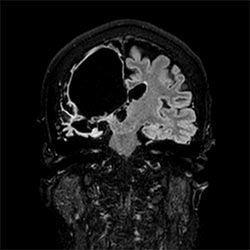

In a society where reimbursements are declining and chronic conditions lead to increased MR procedures and longer waiting times, there is ever increasing pressure on the radiology department. Today, further attempts to accelerate, compromise image quality or are limited to a narrow range of scans. Therefore, to meet the increased demand for productivity, a technology break-through in acceleration is still required. Leveraging our long standing leadership position in speed (i.e. SENSE), Philips brings compressed SENSE, a breakthrough in productivity.

Learn more about the main principles of Compressed SENSE and how it introduces a paradigm shift in productivity, how Compressed SENSE was designed around image quality, and how it advances productivity for clinical MR imaging.

Read about the experiences from Kantonsspital Winterthur (Switzerland) who experienced Compressed SENSE to be a simple yet powerful way to accelerate MRI scanning for different contrast types and sequences, in 2D as well as 3D.